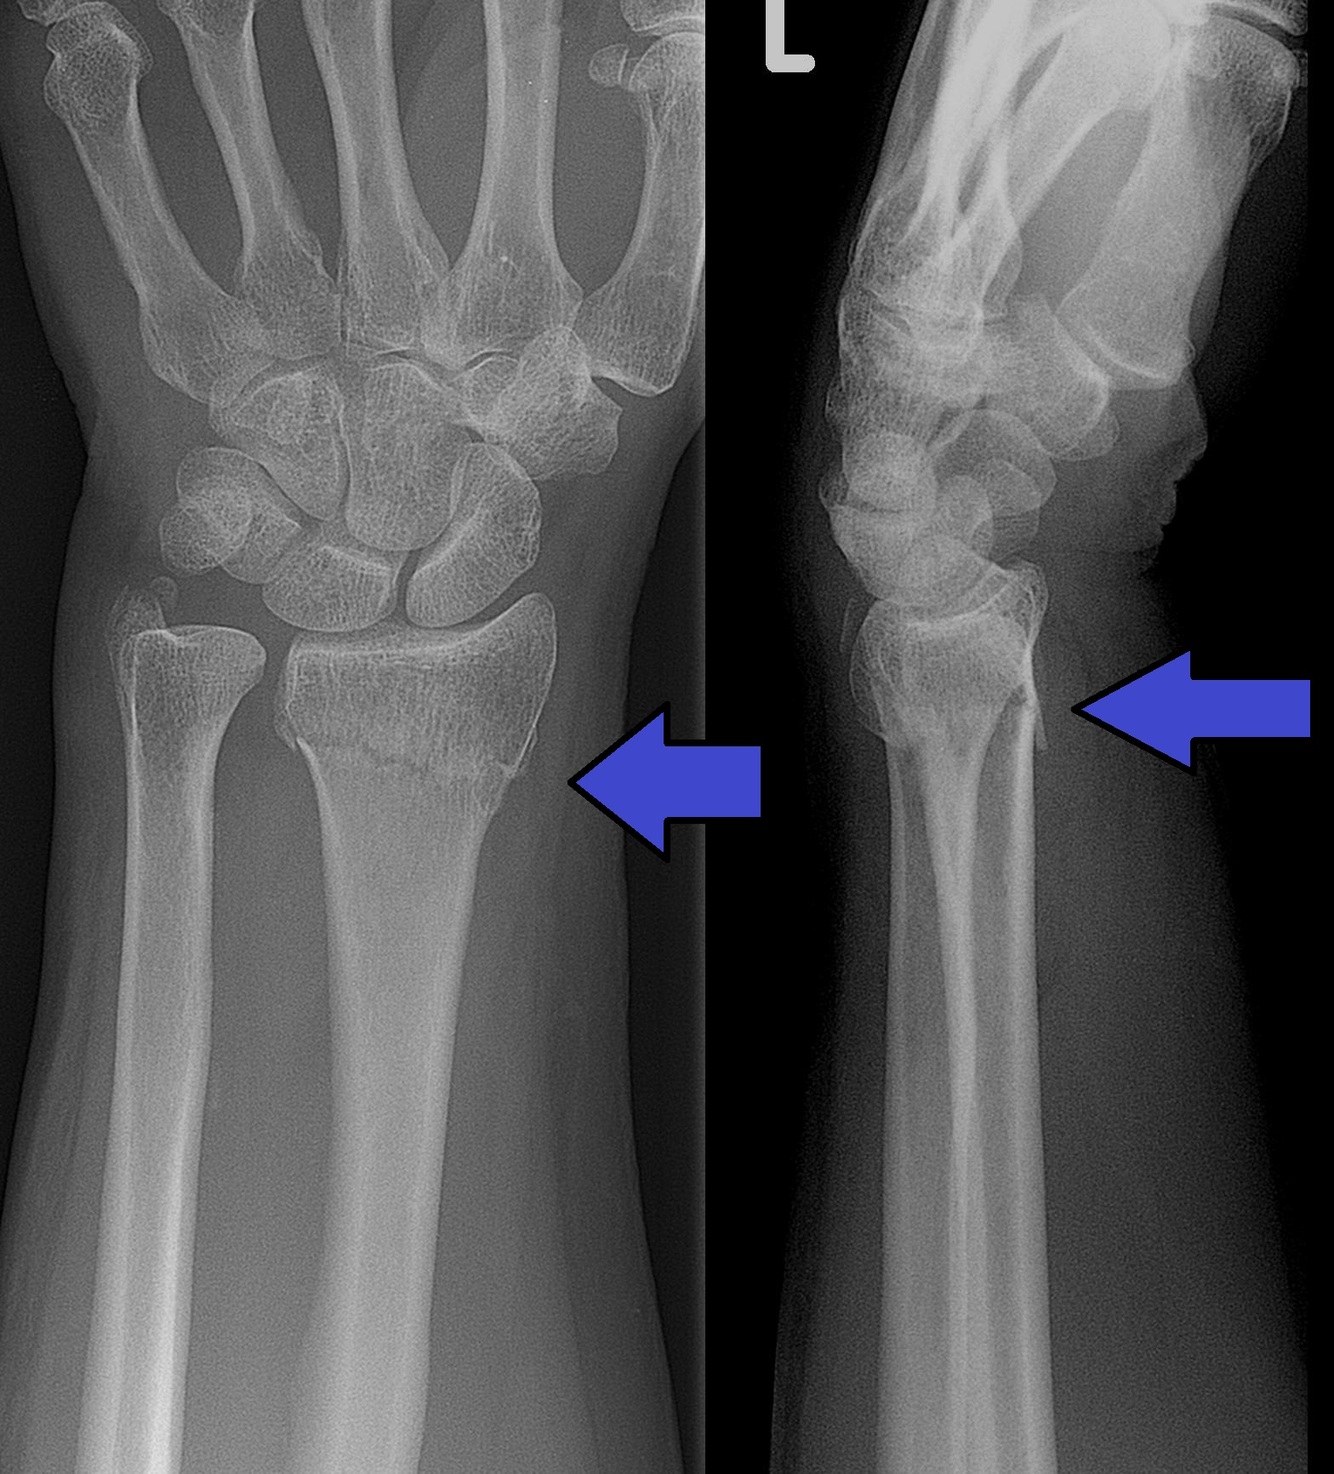

Colles fracture